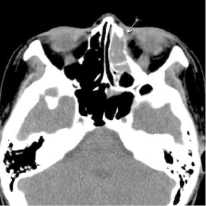

29.09.2016 г. была произведена мультисрезовая спиральная компьютерная томография челюстно-лицевой области. В верхнечелюстной пазухе, передних, средних клетках решетчатого лабиринта и лобной пазухе слева определяется гетерогенное патологическое содержимое, КТ-плотностью от +21,7 ед.Н. до +39,0 ед.Н., с четкими контурами, максимальным размером до 62,0х48,0 мм в поперечнике, на фоне которого визуализируются очажки кальцинации, а также неполностью лизированные костные фрагменты. Определяется остеодеструкция нижних отделов всех стенок верхнечелюстной пазухи, клеток решетчатой кости, а также передних отделов медиальной стенки орбиты слева. Остеодеструкция носит смешанный характер за счет инфильтративного остеолизиса и атрофии от давления. Частично сохранные стенки верхнечелюстной пазухи слева утолщены, в сравнении с контрлатеральной стороной (остеопериостоз). Через вышеперечисленные костные дефекты патологическое содержимое распространяется в одноименную полость носа, мягкие ткани щечной области, ретромаксилярное пространство, а также в передне-медиальные отделы орбиты. Носовая перегородка искривлена вправо. Носоглотка и другие околоносовые пазухи без особенностей.

Заключение: КТ-данные за гетерогенное остеодеструктивное объемное образование околоносовых пазух слева с интраорбитальным распространением (новообразование?). Описанные изменения представлены на рис. 1-2.

Рис. 2. На аксиальном КТ-срезе выявляется патологическое содержимое в клетках решетчатого лабиринта слева с остеодеструкцией передних отделов медиальной стенки орбиты слева